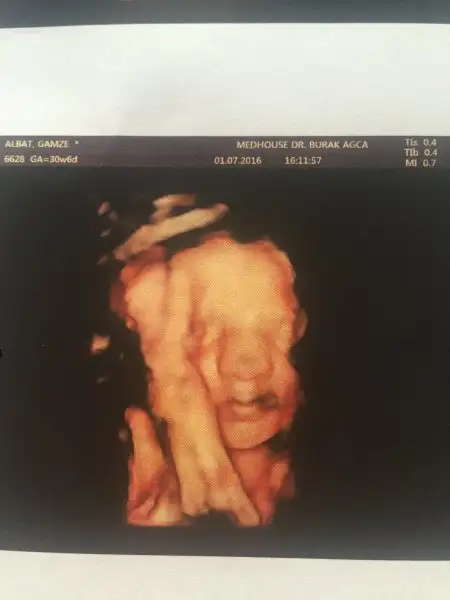

Kızlar merhaba. Az önce doktordan geldik biz. Benim koca burunlu kız 10 gün ilerde çıktı haftasından. 31 hafta 1 günlük olmuşuz. Kilosu 1658 gr boyu da 42 cm. Doğum tarihimiz de 1 eylül olarak güncellendi. Ben de toplamda 6 kg ile devam ediyorum serüvene. İnşallah böyle devam eder. :KK68:Bu arada hepinize iyi kandiller dilerim. :)